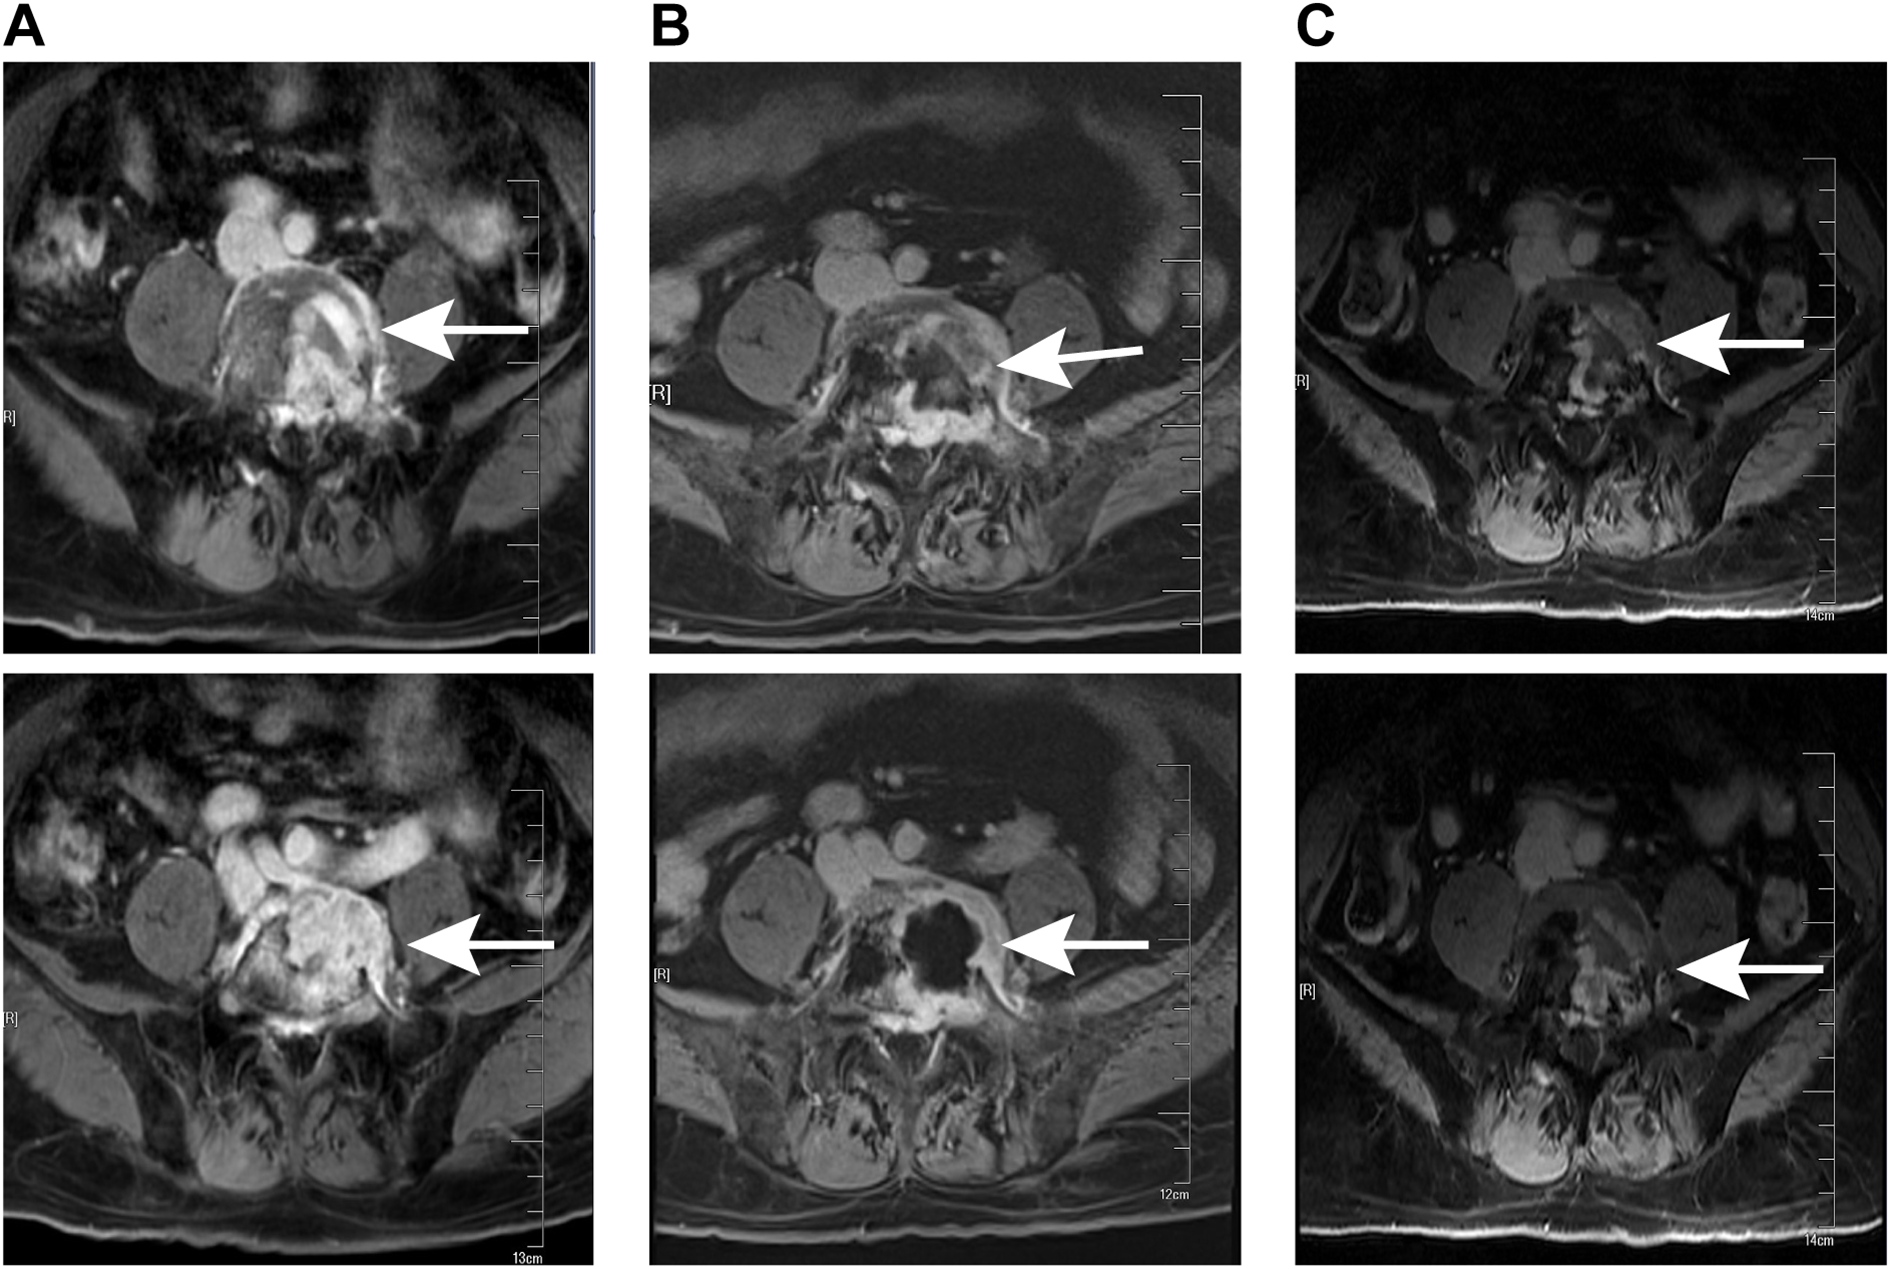

Lumbar MRI examination revealed abnormal signal intensity with T1 prolongation and T2 shortening in the left side of the L5 vertebral body and the left pedicle, accompanied by a protrusion toward the left posterior region. The anterior and superior margins of the vertebra exhibited irregular contours, and contrast-enhanced imaging demonstrated heterogeneous enhancement, suggestive of invasive changes, raising suspicion for tumor involvement (Figure 1A). Subsequent PET-CT examination identified osteolytic bone destruction with irregular borders, areas of sclerosis, and soft tissue mass formation in the corresponding region. Following intravenous administration of the tracer 18F-FDG, there was increased radiotracer uptake, with a maximum standard uptake value (SUV) value of 10.7, further supporting the likelihood of a neoplastic process (Figure 2). The blood test results showed no significant abnormalities.

Figure 1

MRI examination at different stages of treatment. (A) Preoperative lumbar MRI showed a lesion in the L5 (white arrows). (B) MRI conducted prior to radiotherapy following the surgical operation revealed the lesion in the L5 (white arrows). (C) The latest follow-up MRI examination indicated that there was no recurrence of the L5 pyramidal lesion (white arrows).

After the surgical procedure, the patient continued to experience significant pain in the left buttock, precluding independent ambulation. The Visual Analogue Scale (VAS) pain score was recorded at 8 points. Following administration of 20 mg oxycodone sustained-release tablets every 12 hours, there was a slight alleviation of pain symptoms, with the VAS pain score decreasing to 4 points. Ambulation remained possible only with reliance on a wheelchair or crutches for slow movement. A follow-up lumbar MRI revealed that the L5 vertebral body was filled with bone cement and exhibited ring enhancement around it (Figure 1B). After multi-disciplinary consultation involving medical oncologists, radiation oncologists, orthopedic surgeons, neurologists, neurosurgeons, imaging specialists, and pain management physicians, local radiotherapy was recommended. Consequently, the patient was referred to the radiotherapy department for treatment. Following completion of positioning and CT scanning, a VMAT plan (60 Gy/30 fractions) was devised under conditions ensuring spinal cord safety. Concurrently, 125 ml of mannitol was administered intravenously daily post-radiotherapy to mitigate spinal cord edema. After receiving 12 Gy/6 fractions of irradiation, the patient’s pain was markedly relieved, with the VAS pain score reducing to 5 points without oral oxycodone sustained-release tablets. The dose of oxycodone sustained-release tablets was subsequently reduced to 10 mg per dose, administered every 12 hours. Following 20 Gy/10 fractions of irradiation, the pain was further significantly alleviated, with the VAS pain score decreasing to 2 points without oral oxycodone sustained-release tablets, enabling the patient to ambulate slowly without crutches. The remaining 40 Gy/20 fractions were continued during the course of radiotherapy. During this period, the patient experienced occasional foot numbness and five episodes of diarrhea, which were effectively managed with antidiarrheal treatment using montmorillonite powder and loperamide. Upon completion of radiotherapy, the patient experienced complete resolution of pain, and normal ambulation was successfully restored. Subsequently, the patient was enrolled in the follow-up phase.

Follow-up evaluations were conducted at 3-month intervals. During each follow-up, the patient underwent a clinical examination, quality-of-life assessment, and lumbar MRI. The lumbar MRI performed 3 months after radiotherapy revealed no abnormal signals in the left portion of the L5 vertebral body or the left pedicle, indicating complete resolution of the lesion (Figure 1C). As of the latest follow-up, there has been no evidence of disease progression or tumor recurrence for over 20 months, and the patient reported no recurrence of pain. Ongoing follow-up will be maintained.